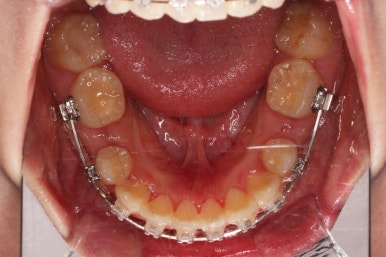

아랫니가 매우 밑으로 많이 내려온게 보이시죠?

과개교합은 비교적 초반에 개선이 되었습니다.

아래 앞니의 높이가 개선된 뒤, 아랫니도 가지런하게 해줍니다.

윗니도 어느새 치아를 뽑은 공간이 많이 줄었네요.